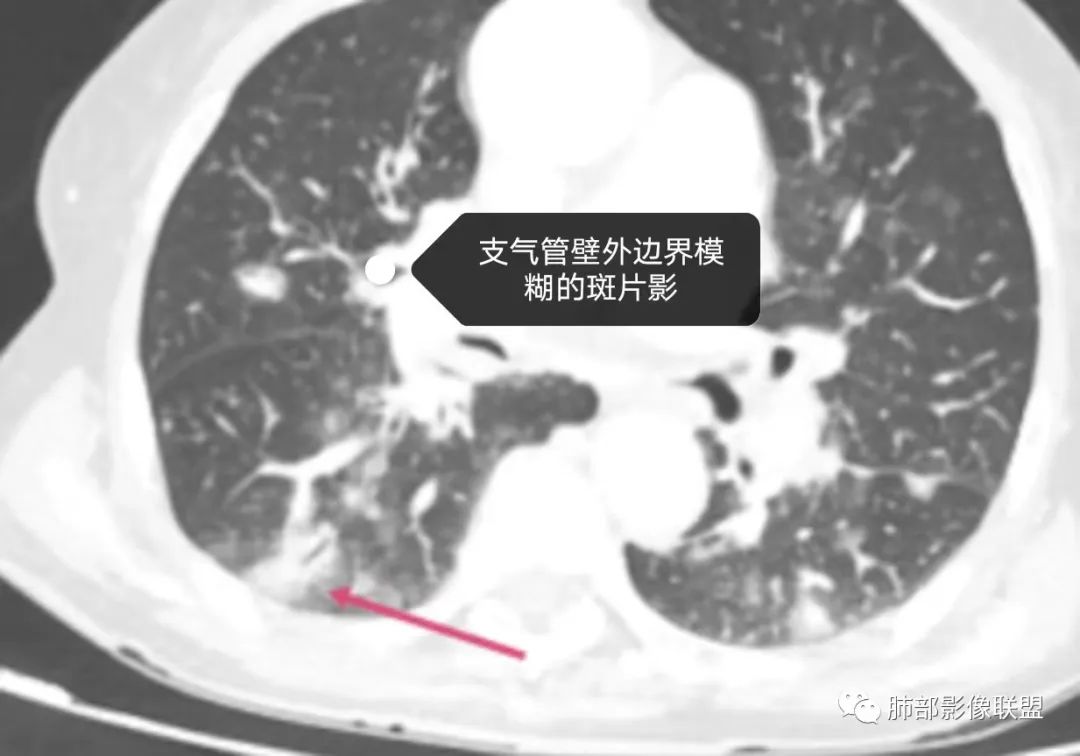

老年女性,三月来两次发热,第一次白细胞计数升高、贫血。第二次白细胞计数不高,LDH升高、低蛋白血症。肺内进行性增多的结节及斑片影,结节见点晕征,斑片影位于支气管血管束,部分支气管壁外见边界模糊的斑片影。有左肾病变。考虑血管炎可能性大。(诊断关键点可能是:点晕征 支气管血管束的斑片影 肾脏病变 第二次发热但白细胞计数不高)

点晕征疾病谱:

1.肿瘤

血管原发肿瘤:血管肉瘤(右房)、上皮样血管内皮瘤、血管内淋巴瘤(大B)

转移瘤:消化生殖系统转移,关注绒癌、恶黑、肠癌

2.感染

真菌:荚膜组织胞浆菌

病毒:疱疹病毒

结核

3.血管炎

4.寄生虫病

5.PCH/PVOD